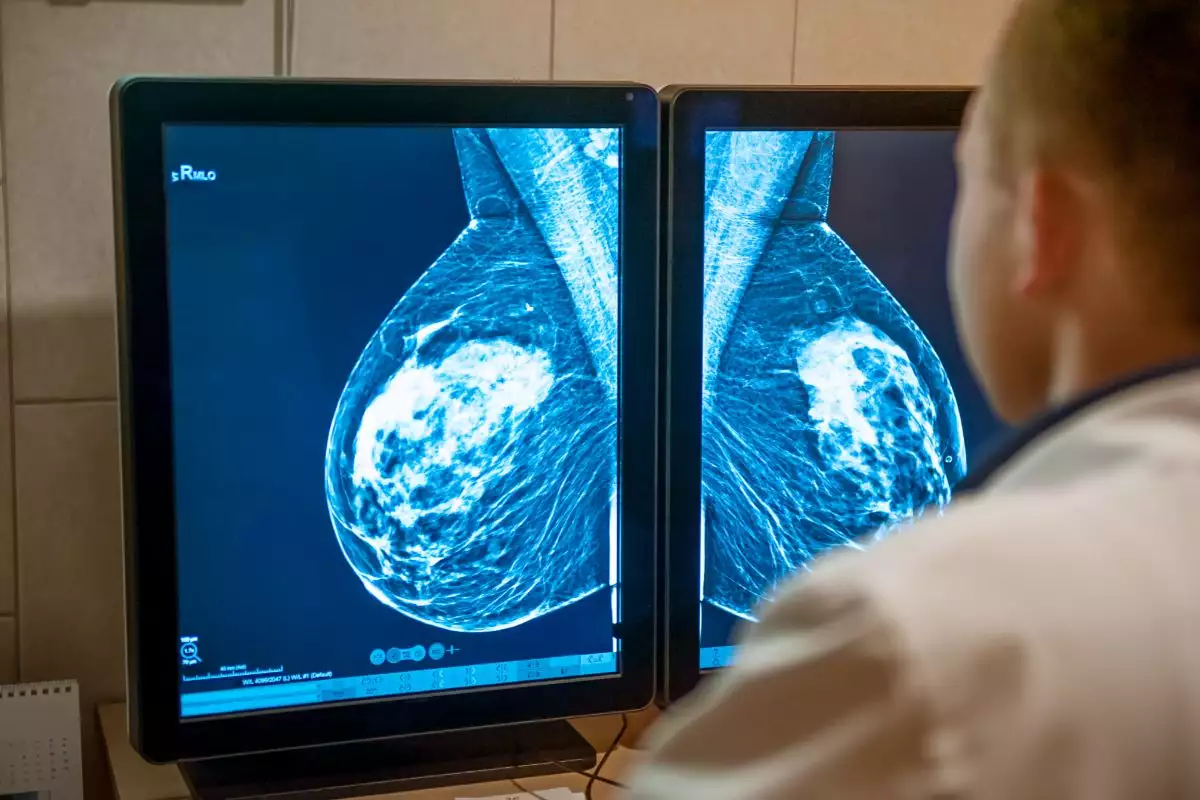

Cobertura de mamografias de rastreamento no SUS foi inferior a 35% em todos os estados

A cobertura de mamografias de rastreamento —exame para prevenir e identificar o câncer de mama em fase inicial – no SUS (Sistema Único de Saúde) em todas as unidades federativas foi inferior a 35% no biênio de 2022 e 2023, aponta relatório do Inca (Instituto Nacional de Câncer) lançado no dia 1º de outubro.

A grande variação entre os estados aponta para uma desigualdade no acesso ao exame: a menor cobertura foi em Roraima, de 6,7%, e a maior no Paraná, 33,6%.

Nos SUS, a mamografia de rastreamento é indicada para mulheres de 50 a 69 anos sem sinais e sintomas de câncer de mama, a cada dois anos. Já o procedimento nomeado apenas como “mamografia” tem finalidade diagnóstica e pode ser feito por pessoas de qualquer idade. Em 2023, foram realizadas 4,4 milhões mamografias em mulheres no SUS, sendo 395,4 mil mamografias e 4,02 mamografias de rastreamento.

Os resultados apontaram ainda que as regiões Norte e Centro-Oeste apresentam a maior parte das suas unidades federativas com menores coberturas (menos de 20%).